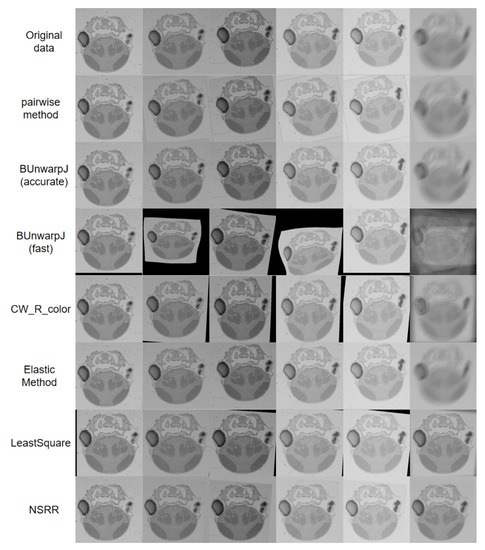

4.2. Comparison with State-of-the-Art Methods

| Method | SSIM | Time |

|---|---|---|

| BUnwarpJ(fast) [10] | 0.6523 ± 0.1235 | 3.6 min |

| BUnwarpJ(accurate) [10] | 0.7037 ± 1.2717 | 4.3 min |

| LeastSquare [8] | 0.8046 ± 0.1578 | 11.729 s |

| Elastic Method [12] | 0.6118 ± 0.0968 | 1.4 min |

| CW_R_color [3] | 0.6721 ± 0.9013 | 36.4 min |

| Pairwise method [23] | 0.7331 ± 0.1283 | 0.937 s |

| NSRR (ours) | 0.8297 ± 0.0706 | 0.2813 s |

| Method | EPE | Time |

| BUnwarpJ(fast) [10] | 16.6243 | 3.4 min |

| BUnwarpJ(accurate) [10] | 14.3140 | 5.5 min |

| LeastSquare [8] | 15.4013 | 5.462 s |

| Elastic Method [12] | 17.6141 | 10.323 s |

| CW_R_color [3] | 12.7754 | 8.1 min |

| Pairwise method [23] | 14.5277 | 0.368 s |

| NSRR (ours) | 11.1903 | 0.289 s |